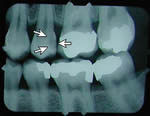

x-ray (previous)

x-ray with cavity

No cavity on first x-ray.

Months later, cavities that start between the teeth can't be seen by visual examination, but they can be detected on an x-ray.

This cavity was detected and filled before the patient felt any discomfort, and before the nerve became infected or the tooth became abscessed.

There is another cavity shown in the X-ray on the right. Can you find it? It's difficult for the untrained eye to spot. Click here to see where it is. (Hint: It's not the left edge of the top left tooth. That's just the edge of the frame around the X-ray).